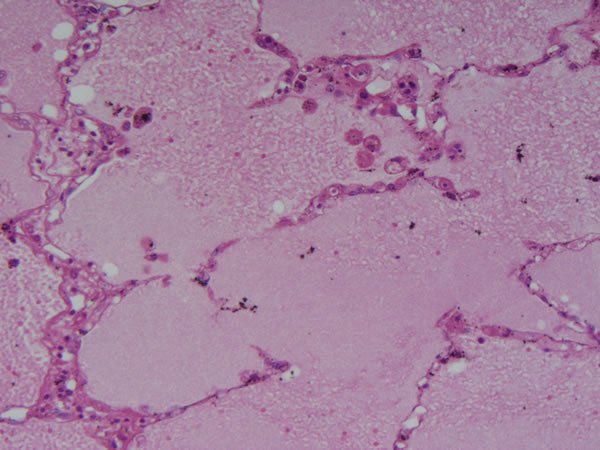

| Pulmão - parênquima pulmonar Edema - edema agudo de pulmão Causas: aumento da permeabilidade vascular | |

Pulmão - parênquima pulmonar Edema - edema agudo de pulmão alvéolos cheios de líquido eosinofílico Causa: aumento da permeabilidade vascular |

Pulmão - parênquima pulmonar Edema - edema agudo de pulmão Achados: Hemorragia intra-alveolar Causa: aumento permeabilidade vascular |

| Pulmão -parênquima pulmonar Edema - edema pulmonar Achados hemorragia, acúmulo de pigmento | |